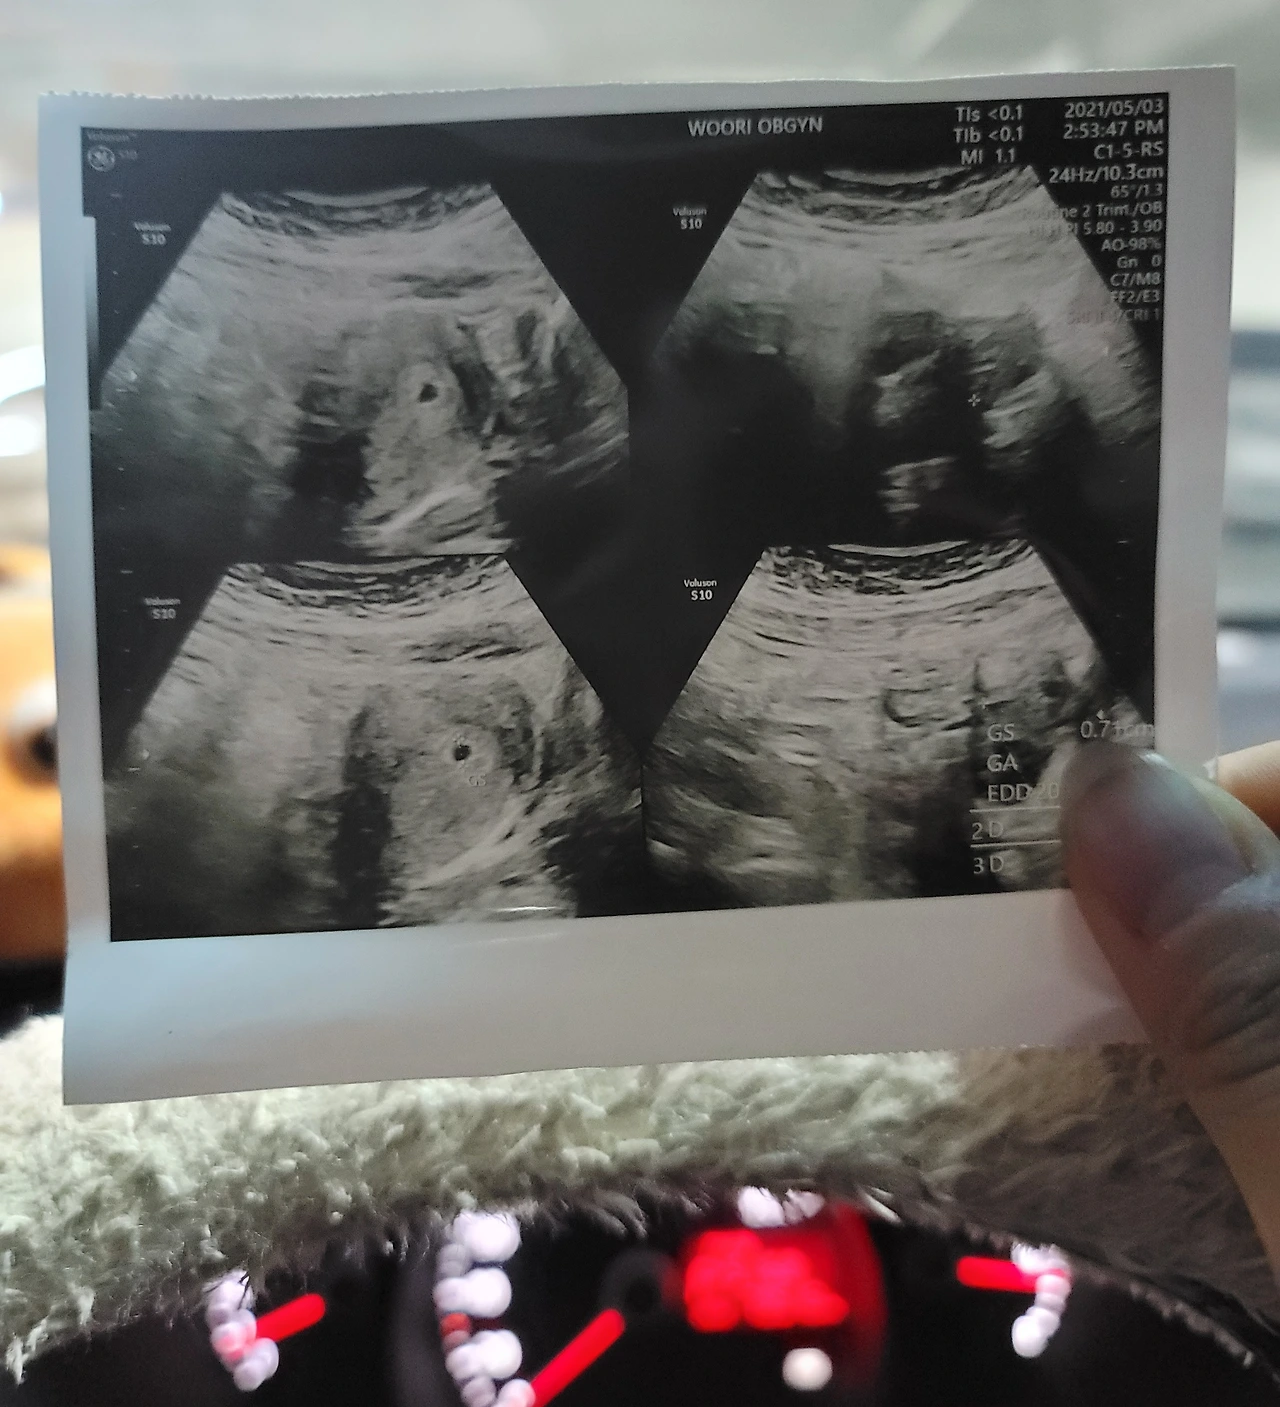

진정되기도 전에 남편에게 알려주겠다고 찍은 첫 사진